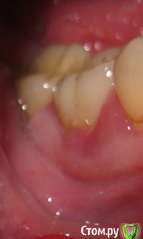

Sparrow Опубликовано 27 февраля, 2018 Поделиться Опубликовано 27 февраля, 2018 (изменено) Уважаемые специалисты.Прошу Вашего мнения относительно моей ситуации. 5 месяцев воспалена десна и сосочек между зубами.При надавливании на край десны из под десны появляются выделения белого цвета в небольшом количестве (буквально по 1 мм вдоль кромки десны). Боли нет ни в десне ни в зубе.Зуб не шатается. На зубе коронка со штифтами - ставили 14 лет назад.При обнаружении воспаления обратилась к стоматологу.Сделан снимок - на снимке ничего не обнаружено - вывод местное воспаление. К такому же выводу пришли впоследствии еще три специалиста - снимок делали еще 2 раза - ничего не находили . За это время (5 месяцев) было сделано 2 чистки - 1 локально - ультразвук под десной - сильно кровоточило и сосочек на следующий день "сдулся" до нормального размера,но выделения остались и через время десна снова увеличилась.Вторая чистка - полностью полость рта. Состояние десны осталось прежним.Выделения есть.Применила уже все возможные варианты полосканий - хлоргексидин-мирамистин-ромашка-сода-парадонтакс-стоматофит - полностью успокоить десну не удается. Обратилась снова к стоматологу. Сделали КТ. Киста на корне зуба и кариес корня под десной. Зуб удалять однозначно или есть еще минимальная возможность его спасти? (мне крайне неудобно показывать вам этот цветной налет на зубах - но это то,что вышло от применения супермягкой щетки Парадонтакс и ополаскивателя Парадонтакс-Экстра за полтора месяца после последней гигиенической чистки) Изменено 27 февраля, 2018 пользователем Sparrow Ссылка на комментарий